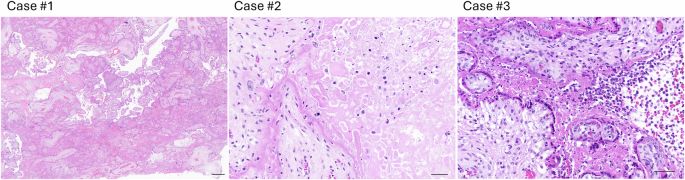

SARS-CoV-2 delta and omicron variants alter trophoblast cell fusion and syncytiotrophoblast dynamics: new insights into placental vulnerability - Cell Death & Disease Cell Death & Disease - SARS-CoV-2 delta and omicron variants alter trophoblast cell fusion and syncytiotrophoblast dynamics: new insights into placental vulnerability

SARS-CoV-2 delta and omicron variants alter trophoblast cell fusion and syncytiotrophoblast dynamics: new insights into placental vulnerability